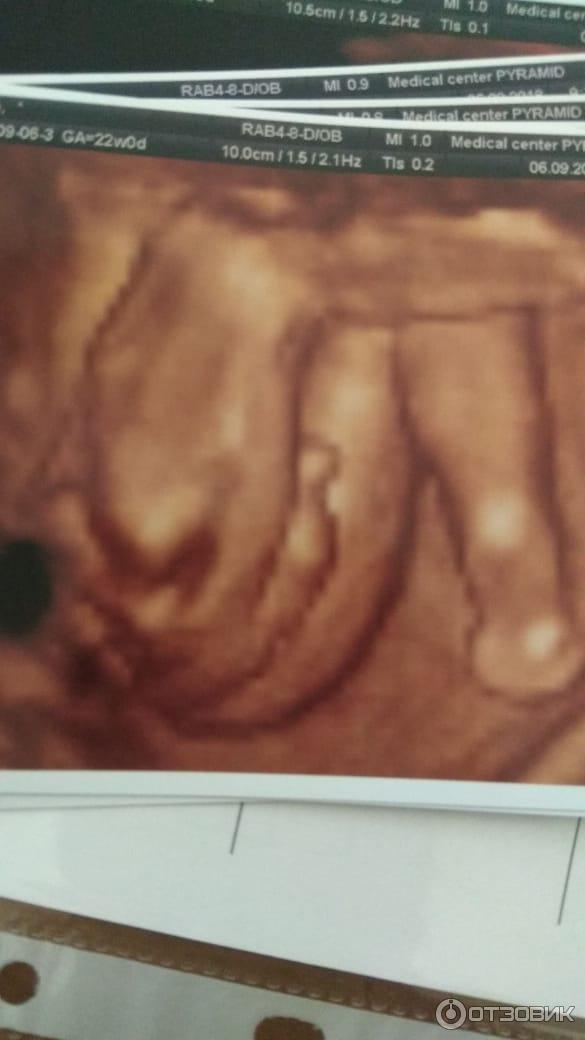

Узи казань лучший

Узи казань лучший 112 фотографий